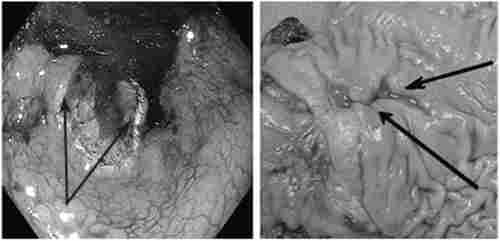

Ендоскопічно на тлі виразкових дефектів відзначаються і ознаки злоякісного процесу (рис. 12.8).

Ендоскопічна картина малігнізованих виразок шлунка

Мал. 12.8. Ендоскопічна картина малігнізованих виразок шлунка